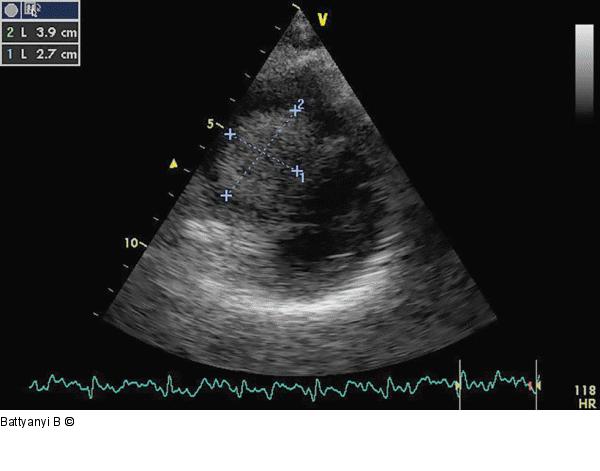

Abbildung 2: Kurze Achse Modifizierte parasternale kurze Achse. Die Anlotung zeigt die in die rechte Herzkammer prolabierende Raumforderung. |

Modifizierte parasternale kurze Achse. Die Anlotung zeigt die in die rechte Herzkammer prolabierende Raumforderung. |